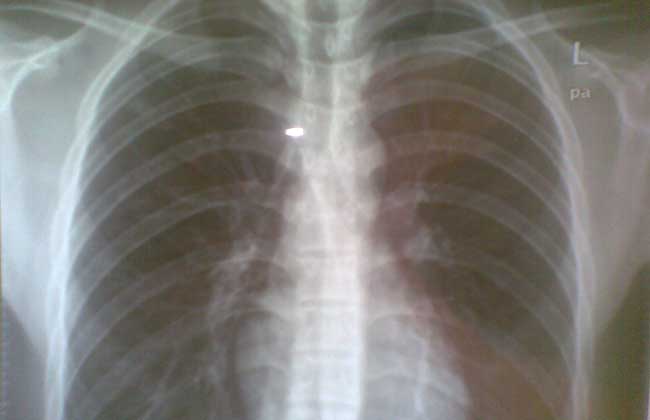

结核性胸膜炎是结核杆菌首次侵入机体所引起的疾病,引起结核性胸膜炎的途径有①肺门淋巴结核的细菌经淋巴管逆流至胸膜。②邻近胸膜的肺结核病灶破溃,使结核杆菌或结核感染的产物直接进入胸膜腔内。③急性或亚急性血行播散性结核引致胸膜炎。④机体的变应性较高,胸膜对结核毒素出现高度反应引起渗出。⑤胸椎结核和肋骨结核向胸膜腔溃破。因为针式胸膜活检或胸腔镜活检已经证实80%结核性胸膜炎壁层胸膜有典型的结核病理改变。因此,结核杆菌直接遍及胸膜是结核性胸膜炎的主要发病机制。